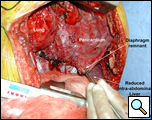

Through a 7th interspace right thoracoabdominal incision, the right lung was decorticated and pneumolysis performed (Figure 5). Once dissection was complete, the liver was found in the pleural space with only a small rim of diaphragm medially (Figure 6). The liver was completely mobilized and reduced into the abdomen, insuring that the right hepatic vein was not kinked. Multiple liver biopsies were obtained. The diaphragm was reconstructed using a 15x25cm 2mm thick polytetrafluoroethylene patch, anchoring it posteriorly near the 10-11th thoracic vertebral level to the posterior mediastinal fascia, laterally around the ribs, and anteriorly to the medial remnant of the diaphragm (Figure 7).